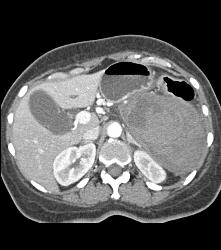

GIST Tumor